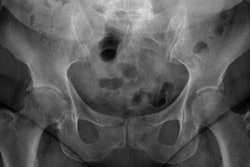

A newborn whole-body phantom.In this study, Elshami and colleagues used a newborn phantom they developed to simulate a neonate undergoing chest x-rays at the University of Sharjah's Medical Imaging Laboratory. The phantom mimics a newborn patient, with a height and weight of 50.9 cm and 2.4 kg.